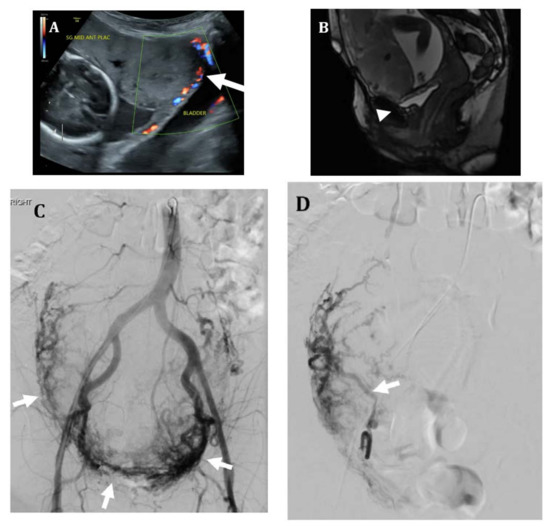

Figure 1.

Thirty-three-year-old female with placenta accreta. (A) Sagittal SSFSE MR image shows a thickened placenta with abnormal lobulated contour and loss of myometrial thickness in the lower uterine segment (arrow), suggestive of placenta accreta. (B) Prophylactic bilateral internal iliac artery occlusion balloons were placed prior to hysterectomy. Patient underwent cesarean hysterectomy at 33 weeks with delivery of a healthy newborn. Pathology showed superficial attachment of the placenta to the uterine wall, consistent with placenta accreta.